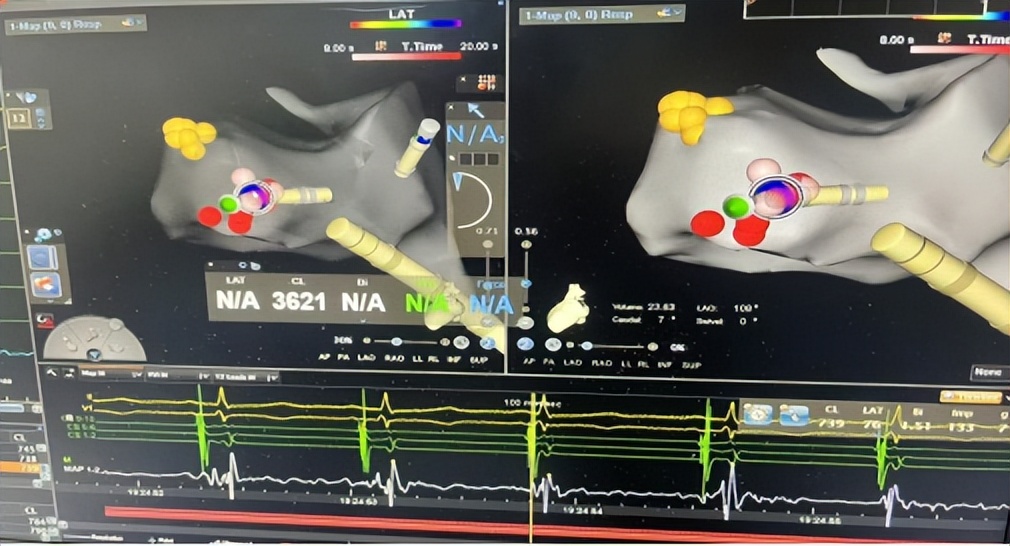

△诱发心律失常过程

△ 消融治疗心律失常中